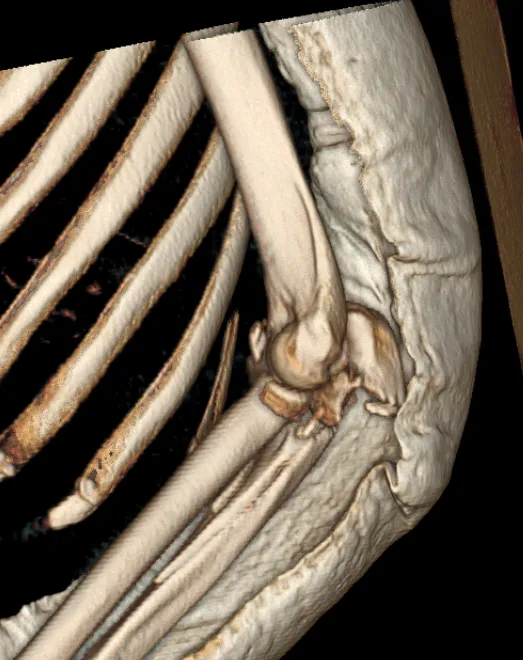

左肘关节CT平扫+三维检查提示

左肘关节面对位欠佳

左尺骨鹰嘴及桡骨头骨折

周围软组织肿胀

图片